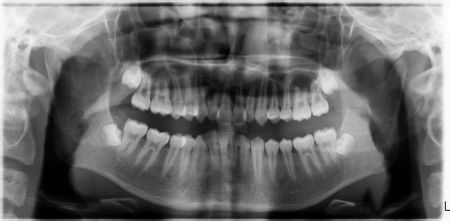

问题:拔牙前为什么需要拍片子?拔牙前为什么要拍光片?在医院和口腔诊所里,我们经常遇到这样的患者朋友,他们对拔牙前拍片特别不理解(特别是一些年龄大的患者),总认为拍片属于变相增加收费……[阅读] - 牙齿美容的全新选择--全瓷贴面[2015-02-26 21:14:01]